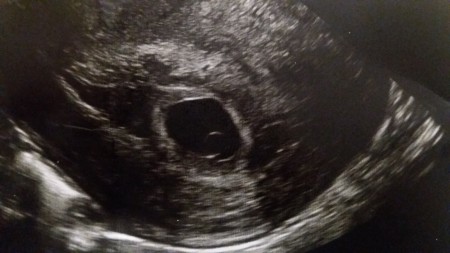

arkadaşlar adetr göre 6. Hafta ultrason göre 5+2 kese var  ama bebeği göremedim 12mm dedi doktor kese için. Bu görüntü hakkında bilgi sahibi olan var mı. ? Bebek kaçıncı haftada keseye giriyor.?

Kese 20 mm olduktan sonra kalp atışının da bebeğin de gözükmesi gerekir. Biraz daha vakti var